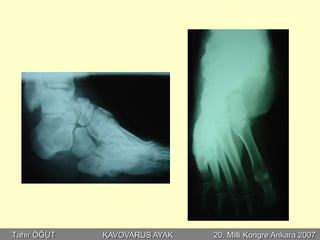

ÜÇLÜ ARTRODEZ

Postop 2. sene

Postop 3. sene

Postop 1. sene